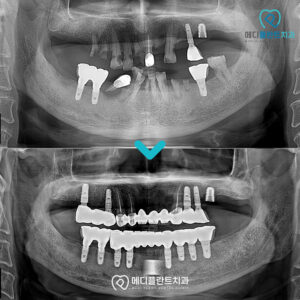

춘천수면치과 편안한 식사와 자연스러운 웃음을 위해! . 안녕하세요 🙂 춘천수면치과 메디플란트치과입니다. . 자연의 섭리에 따라 나이가 들면 누구나 노화 현상을 겪게 되는데요. . 신체 기능의 저하뿐 아니라 치아의 기능적인 부분…